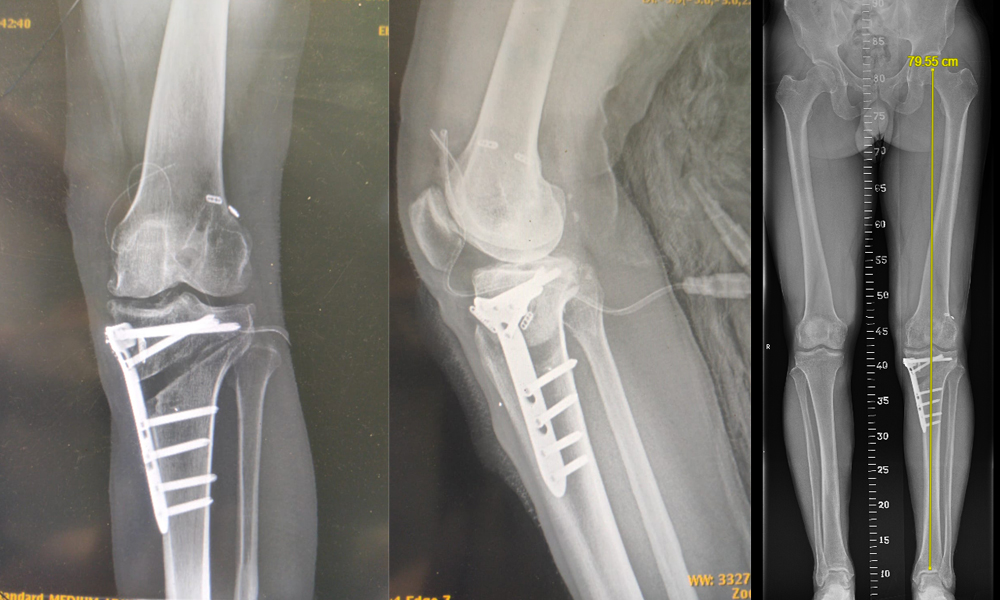

Yüksek Tibial Osteotomi

Bir tibial osteotomide, bacağı düzeltmek için bir kemik kaması çıkarılır. Diz artriti için yapılan çoğu osteotomi, dizin iç kısmına çok fazla baskı uygulayan kavisli bir hizalamayı düzeltmek için tibia (kaval kemiği) üzerinde yapılır. Bu işlem sırasında, tibianın iç yüzeyinden, dizin eğri ve kireçli tarafının altından bir kemik kesisi yapar. Cerrah kamayı şeklinde bu kesiği araladığında bacağını düzeltir. Bu, dizin sağlıklı tarafındaki kemikleri birbirine yaklaştırır ve hasarlı, artritik taraftaki kemikler arasında daha fazla boşluk oluşturur. Sonuç olarak, diz, ağrılı taraftaki baskıyı hafifleterek ağırlığı daha eşit bir şekilde taşıyabilir.

Uyluk kemiğinin (femur) osteotomileri aynı teknik kullanılarak yapılır. Genellikle çarpık bir hizalamayı düzeltmek için yapılırlar.